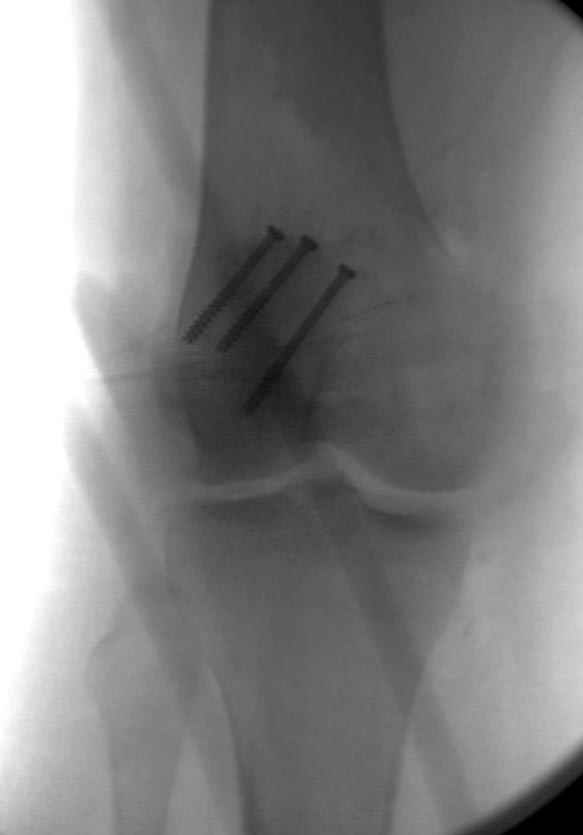

Сегодня досылаю остальные снимки, которые не прошли вчера. Как вчера писал, после фиксации перелома надколенника с дефектом кости и собственной связки, наложили ваккуум и наружный фиксатор. (снимки 4-9)

Внешний фиксатор держим около 6 недель, поэтому был выбран метод фиксации шурупами и еще линия перелома была диагональной, не было нужды в tension band technique, cannulated screws удобнее, провел спицы и по ним шурупы.

На операции: Irrigation&Debridment около 10 литров раствора, по два стержня в сегменте, фиксация диагонального, с дефектом, перелома надколенника тремя cannulated 4мм шурупами, ушивание поперечного разрыва связки 5.0 Ethibon sutures, разрыв находился на 2 см ниже надколенника (срез чем-то острым), повторная ирригация раны, взятие посева на аэробическую и анэробическую культуру, окончательная фиксация стержней наружного фиксатора 50см Carbon Fiber Bars, вакуумное закрытие. Мониторинг показал, что компартмент синдрома нет.